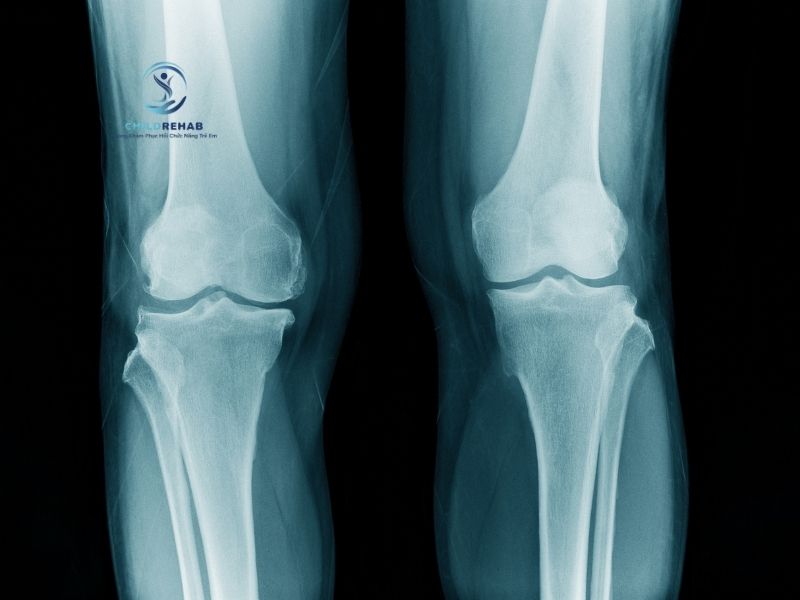

Không phải trường hợp nào chân chữ X ở trẻ cũng cần chụp X-quang. Tìm hiểu khi nào cần thêm đánh giá hình ảnh.